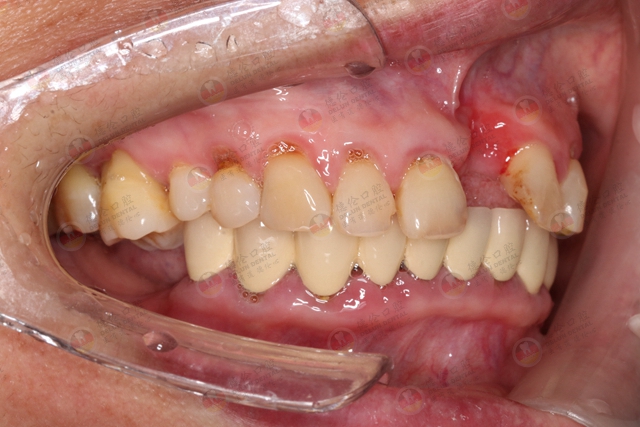

牙周炎的相关症状

早期症状不明显,患者通常只有继发性的牙龈出血或口臭表现,与龈炎症状相似。检查可见龈缘、龈乳头和附着龈的肿胀、质松软,呈深红色或暗红色,探诊易出血。随着炎症的进一步扩散,出现下列症状: